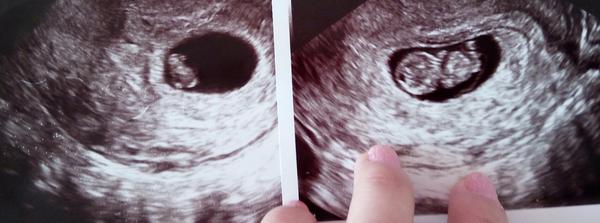

@anetka582 V kolikátém tt je ta první fotka? 🙂

Ta první fotka je 7 TT 🙂

@anetka582 Tak to je mega rozdíl. Jinak gratuluji 🙂

Je 😁 na první fotce má 9 mm a po 14 dnech měl už 2,5 cm. Doufám , že nebudu mít doma basketbalový tým 😁